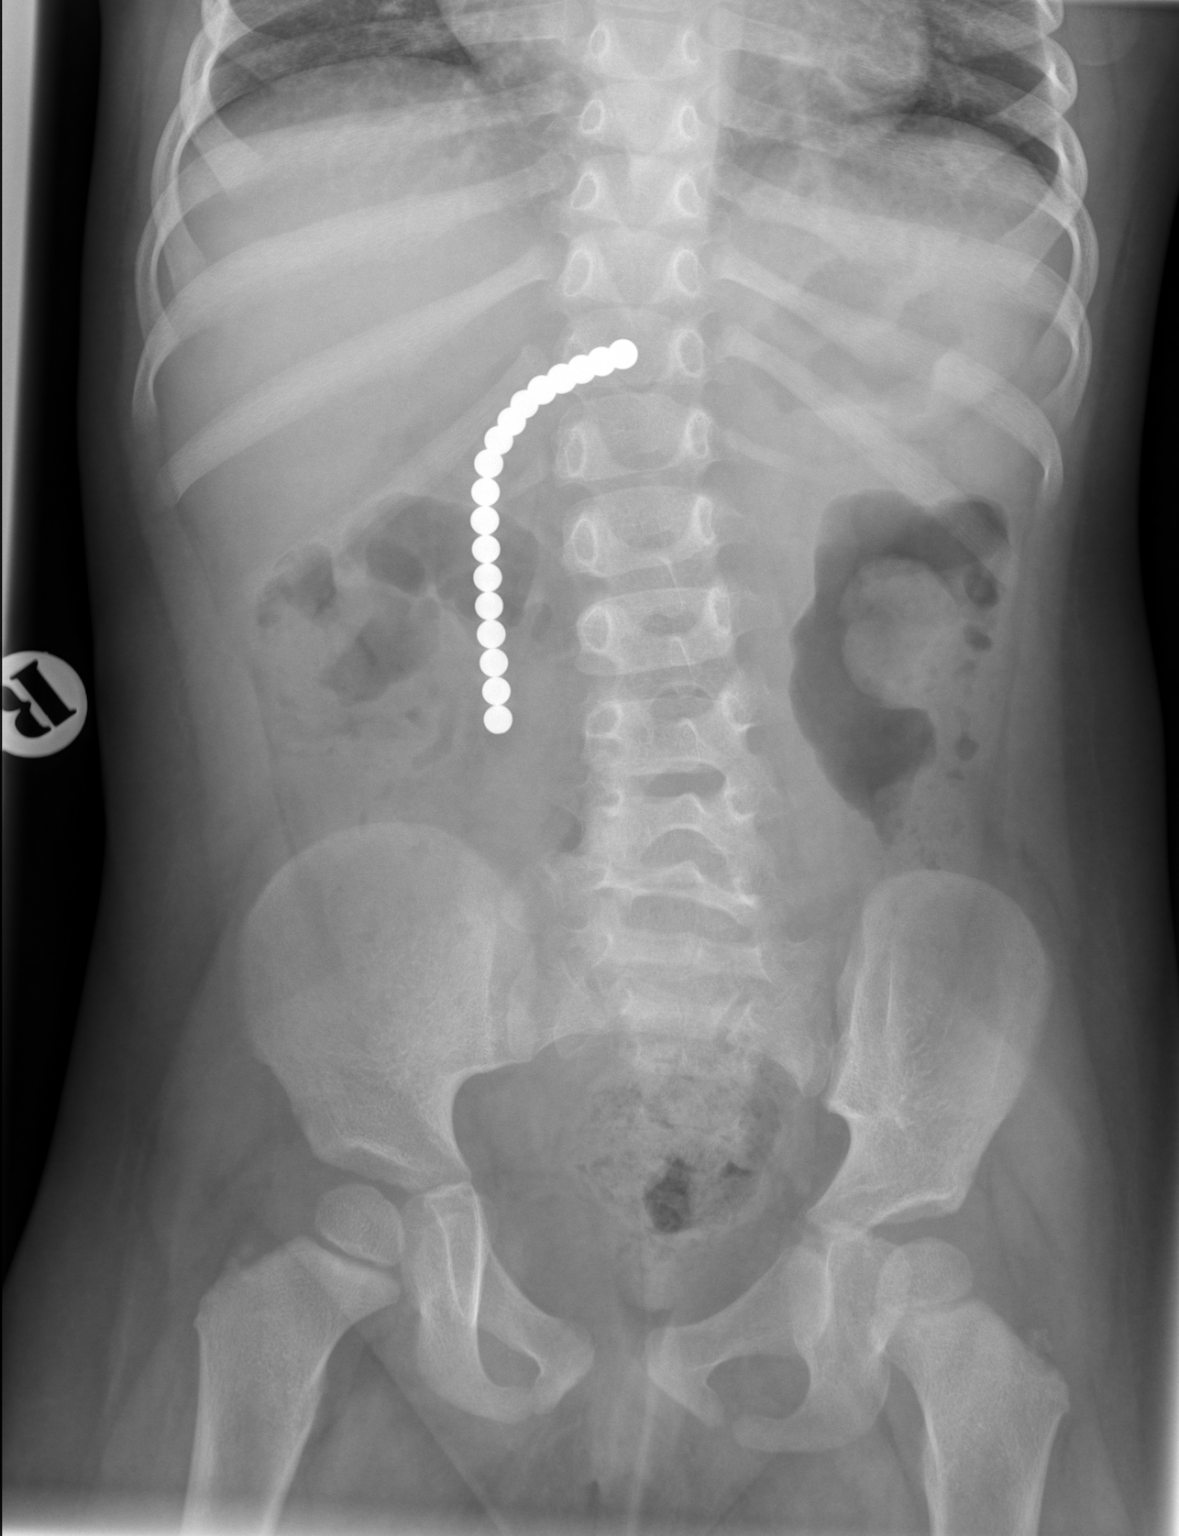

Kid Swallowed Small Plastic Ball. if your child experiences any of the following symptoms after swallowing something, contact your child’s doctor or go to the closest. Symptoms include chest pain, coughing, gagging, difficulty breathing, vomiting, and abdominal pain. your child may show no symptoms at all after swallowing an odd item. learn more about swallowed foreign object including types of objects swallowed by children and button. But clues that something’s amiss. if you think your child swallowed something small that isn’t sharp (like a plastic bead), you do not need to take him or her to the. if you swallow a foreign object, it usually will pass through your system without notice. a swallowed foreign object is one that is not supposed to be in the gastrointestinal tract. this leaflet is intended to advise you of the procedure for managing a child who has swallowed something (a foreign object). The objects posing the greatest risks include sharp objects, broken glass, batteries, and magnets.

if you think your child swallowed something small that isn’t sharp (like a plastic bead), you do not need to take him or her to the. this leaflet is intended to advise you of the procedure for managing a child who has swallowed something (a foreign object). The objects posing the greatest risks include sharp objects, broken glass, batteries, and magnets. your child may show no symptoms at all after swallowing an odd item. a swallowed foreign object is one that is not supposed to be in the gastrointestinal tract. if your child experiences any of the following symptoms after swallowing something, contact your child’s doctor or go to the closest. if you swallow a foreign object, it usually will pass through your system without notice. Symptoms include chest pain, coughing, gagging, difficulty breathing, vomiting, and abdominal pain. learn more about swallowed foreign object including types of objects swallowed by children and button. But clues that something’s amiss.